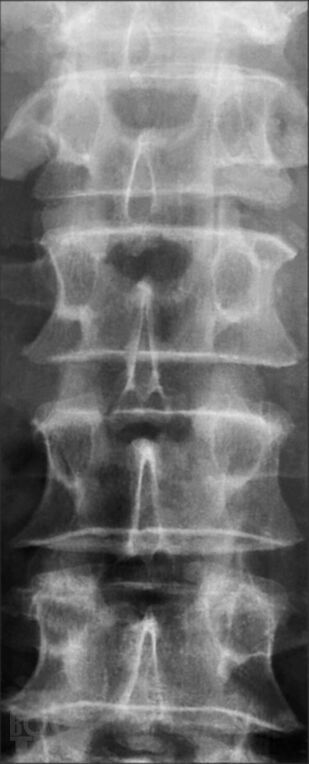

В руководстве изложены общие аспекты артрологии (строение и функция суставов, классификация основных заболеваний суставов, методы диагностики и терапии заболеваний суставов, оценка нарушения функции суставов), особенности клиники, ди агностики, дифференциальной диагностики наиболее частой костносуставной патологии — остеопороза, остеоартроза, ревматоидного артрита, анкилозирующего спондилоартрита, псориатического артрита, подагры, паранеопластического артрита и поражений околосуставного аппарата. В книге отражены особенности суставной патологии в пожилом возрасте.